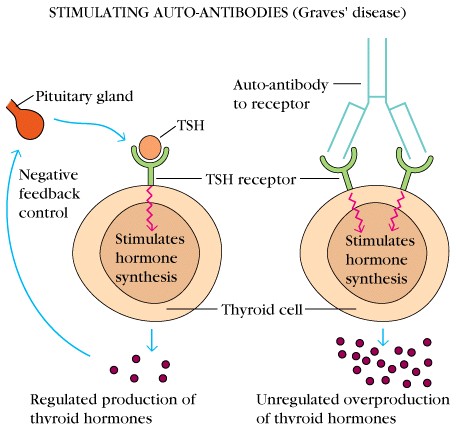

45_10GravesDisease_UP

45_Graves

graves.html